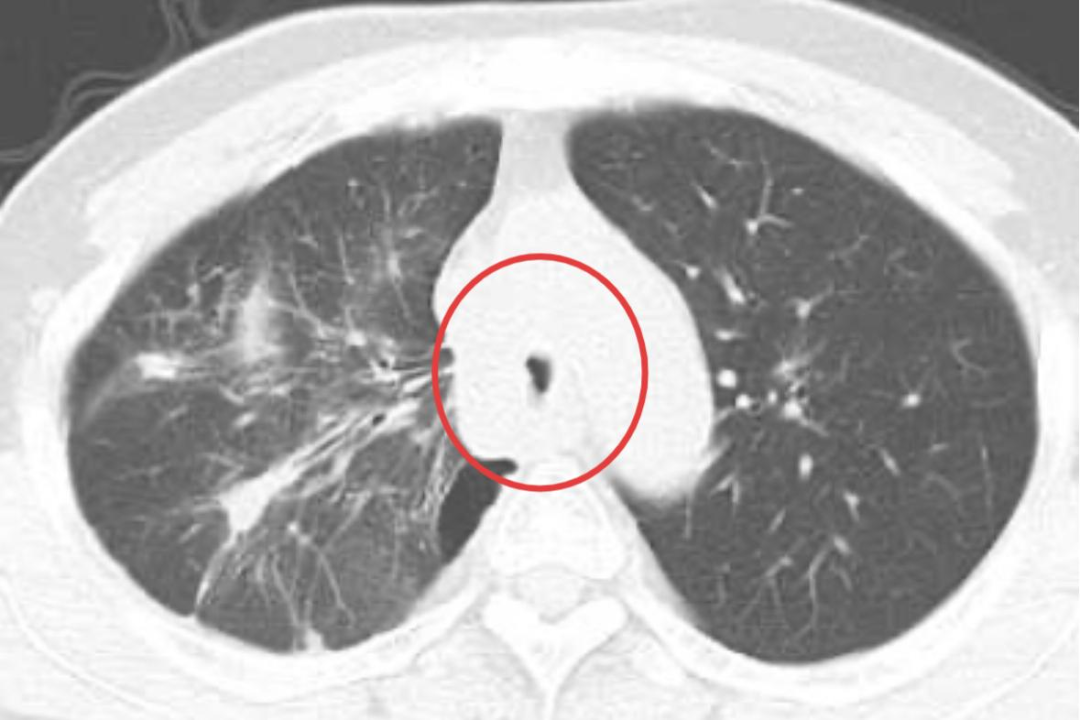

近日,贵州航天医院呼吸与危重症医学科紧急为一名主气道被肿瘤严重堵塞的肺癌患者成功实施了全麻硬质支气管镜下气道内综合治疗术,生动诠释了医者对生命的敬畏,也体现了该团队以技术守护生命的深厚功底。 53岁的陈先生(化名)近半年来感觉气促逐渐加重。5个月前,他在外院确诊为右肺中央型鳞状细胞癌,使用了化疗及免疫治疗。最近半个月,喘息、呼吸困难进一步加剧,已连续多日因严重呼吸困难无法平卧,外院胸部CT显示:肿瘤已侵犯并导致主气道(隆突水平)重度狭窄甚至接近闭塞,存在急性窒息风险。鉴于气道梗阻进展迅速且已超出常规药物及支持治疗的缓解能力,外院评估暂不具备开展介入性气道开通的条件,病情危重,亟需紧急气道干预。 患者就诊于贵州航天医院时,已处于明显呼吸衰竭状态,血氧饱和度一度跌至79%(正常人一般在95%以上),生命垂危。 时间就是生命!经我院呼吸与危重症医学科呼吸介入团队紧急评估,该患者为高危中央型气道重度狭窄,病情危急,随时存在因气道完全阻塞导致急性呼吸衰竭甚至窒息的风险。当务之急是立即进行气管镜下精准评估,并根据狭窄位置、形态与程度,制定个体化介入治疗方案,以迅速解除气道梗阻,为后续综合治疗争取时间。 在与患者及家属沟通病情并征得同意后,呼吸介入团队立即在静脉舒适麻醉下行电子支气管镜检查,从镜下看到患者气管中下段被肿瘤组织阻塞,管腔狭窄高达80%,并且肿瘤呈浸润性生长侵犯至左、右两侧主支气管,于是团队当机立断,转为实施全麻硬质支气管镜下气道内综合治疗术。 医生将硬质支气管镜(一根中空的金属管道)经口置入患者主气道,在确保通气的同时,为后续操作建立了稳固的“工作通道”。手术中,首先在气管内严重狭窄处实施高频电刀切除部分肿瘤组织,然后再用高频电凝对基底部和易出血部位进行精准消融及止血,将堵塞“生命通道”的肿瘤逐步清理。 高频电刀切除 部分肿瘤组织 高频电凝 消融 由于肿瘤侵犯范围较大且生长快,单纯切除后气道壁仍有塌陷及再次阻塞的风险,为确保气道长期通畅,团队在气管狭窄最严重的部位,精准置入Y型镍钛合金覆膜气道支架。支架像一把撑开的“小伞”,瞬间将狭窄的气道撑开,恢复了气流的顺畅通过。 置入Y型镍钛合金覆膜气道支架 术后,陈先生转入病房进一步观察治疗,氧饱和度迅速回升至正常水平,呼吸困难随即缓解。这场成功的急救,不仅畅通患者的呼吸,也使其重获接受后续抗肿瘤治疗的机会。 贵州航天医院精品技术 硬质支气管镜介入治疗 硬质支气管镜介入治疗是处理复杂中央气道狭窄与阻塞的关键核心技术,本身是一个中空的金属管道,它在手术中扮演着多重关键角色: 可靠的通气保障:在全麻下,它本身可作为通气管道,维持患者在整个手术过程中的呼吸,为医生在气道内的复杂操作提供了充足的安全时间和稳定的操作平台。 稳固的操作通道:其宽阔的管腔允许多种治疗器械(如电刀、支架、冷冻探头等)同时或交替进入,便于进行高效、综合的介入治疗。 处理大出血能力强:对于富含血管的肿瘤,操作中一旦发生出血,硬镜能快速压迫止血或保证吸引效率,是处理高风险出血的重要安全保障。 贵州航天医院呼吸与危重症医学科是国家临床重点专科建设单位、贵州省医学重点学科、临床重点专科、贵州省基层医院介入培训基地,遵义市医学重点学科、临床重点专科,是贵州省内呼吸疾病诊疗规模最大、诊疗项目最全的呼吸疾病品牌科室。现开放床位350张,设有4个病区、RICU、呼吸介入诊疗中心、慢病康复治疗中心和呼吸疾病研究中心实验室,在肺癌与肺结节、慢性阻塞性肺疾病、肺炎、肺结核等呼吸系统疾病的诊疗方面形成了区域特色优势。 贵州航天医院 呼吸与危重症医学科专家简介 廖江荣 国务院政府特殊津贴专家 遵义市呼吸疾病临床医学中心 学科带头人 二级教授 硕士研究生导师 主任医师 学术任职: 亚洲冷冻治疗学会副主席 中国医药教育协会介入微创专业委员会呼吸分会副主任委员 中国防痨协会超声专业委员会副主任委员 中国抗癌协会肿瘤微创治疗专业委员会常务委员 中国防痨协会多学科诊疗专业委员会常务委员 中国医疗保健国际交流促进会结核病学分会常务委员 第一届中国人体健康科技促进会呼吸介入专业委员会常务委员 中国抗癌协会第一届肿瘤组织间植入治疗专业委员会常务委员 西部呼吸介入联盟副理事长 贵州省医学会呼吸病学分会第六届委员会副主任委员 贵州省中西医结合呼吸专业委员会副主任委员 贵州省医学会结核病分会常务委员 遵义市呼吸内科专业医疗质控中心主任委员 遵义市中西医结合学会理事长 专业擅长: 呼吸系统(肺)疑难病的诊断及危重病的抢救,呼吸系统(肺)感染性、疑难性疾病介入快速诊断(ROSE),尤其在肺癌、肺小结节早期诊断,肺癌微创综合靶向治疗,难治性、复治性、重症肺结核诊疗,硬质支气管下复杂性气道狭窄诊治,纤支镜介入治疗气道肿瘤、结核、气道狭窄(球囊扩张、支架植入、高频电刀、氩气刀、冷冻、灌洗、注药、微波消融),间质性肺疾病的诊疗上具有极高水平;带领团队勇于创新,在贵州省率先开展多项新技术、新疗法,如CT引导下及纤支镜下I125粒子植入及CT引导下微波、冷冻消融介入治疗肺癌等多项新技术,带动了贵州省肺部疾病的介入治疗水平提高。 蒋 婷 贵州航天医院党委委员、副院长,副主任医师 专业擅长:从医20余年,在呼吸系统疾病、介入呼吸病学、肺部结核、肺部肿瘤等方面具有丰富的临床经验和专业技能,尤其是慢性阻塞性肺疾病、支气管扩张、肺结核、耐药肺结核、肺癌、胸腔积液等肺部疾病的诊治、微创介入、危重病患者抢救。 现任中国防痨协会结核病与糖尿病专业分会副主任委员,中国女医师协会第一届介入专业委员会委员,贵州省基层呼吸疾病防治联盟-间质性肺疾病联盟委员,贵州省防痨协会第七届理事会理事,贵州省中西医结合学会呼吸专业委员介入呼吸病学组委员,贵州省遵义市中医药学会中西医结合肺病(呼吸)分会副主任委员,贵州省遵义市中医药学会中医肿瘤专业委员会常委;发表论文数篇,参与并主持多项科研项目。 唐永江 四川大学华西医院 呼吸与危重症医学科 副主任医师 呼吸危重症医疗组长 香港中文大学博士 美国康奈尔大学访问学者 贵州航天医院 呼吸与危重症医学科 学科带头人 主要从事呼吸危重症(特别是呼吸重症感染)的临床及科研工作。 PCCM专培结业医师 中华医学会呼吸病学分会呼吸危重症学组秘书 中华医学会呼吸病学分会ECMO工作组成员 四川省医学会呼吸病学专委会介入学组委员兼秘书 发表文章20余篇,主持及参与多项国家自然科学基金及省卫健委基金。 周裕祥 呼吸、感染党支部书记,呼吸与危重症医学科总负责人,副主任医师 专业擅长:对经皮穿刺肺活检、肺结节、肺癌的微创介入诊疗具有丰富的临床经验。 贵州省中西医结合学会呼吸专业委员会介入呼吸病学组常务委员,中国医师协会呼吸医师分会介入呼吸病学工作委员会呼吸病血管介入学组委员,贵州省中西医结合学会呼吸学分会委员,遵义市医学会放射肿瘤治疗学分会委员,中国医药教育协会介入微创呼吸分会委员,北京健康促进会中青年专家委员会胸部疾病精准活检分委会委员;曾赴重庆医科大学RICU、珠海市人民医院介入科进修学习。 王 云 中共党员,呼吸与危重症医学科一病区主任,副主任医师 专业擅长:擅长呼吸系统常见病及疑难危重症、介入呼吸病学、肺部肿瘤疾病的诊治,尤其擅长快速现场评价(ROSE)技术。 贵州省中西医结合学会呼吸专业委员会介入呼吸病学组委员,遵义市中医药学会中西医结合肺病(呼吸)分会委员,贵州省中西医结合学会第六届呼吸专业委员会委员。 杨 芳 中共党员,呼吸与危重症医学科二病区、内镜中心主任,副主任医师 专业擅长:从事临床工作约20年,对呼吸危重病的救治有独到的见解,尤其擅长呼吸系统疾病的介入诊疗,对呼吸内镜下的诊治及经皮肺穿刺诊疗技术具有丰富的临床经验。 亚洲冷冻治疗学会委员,中国医药教育协会介入微创呼吸分会委员,西南结核病医院联盟第二届委员会秘书/委员,贵州省中西医结合学会第六届呼吸科专业委员会委员,贵州省中西医结合学会呼吸专业委员会介入呼吸病学组秘书,贵州省中西医结合学会呼吸专业委员会基层康复学组副组长,贵州水利电力医学科学技术会高原医学分会委员,遵义市中医院学会中西医结合肺病(呼吸)分会秘书/常务委员,遵义市医学会肿瘤学分会(第二届)委员,遵义市医学会放射肿瘤治疗学分会第二届委员;主持及参与科研课题多项,参编著作《呼吸内镜操作技术规范》、《介入结核病学》,发表论文数篇。 李桂凤 中共党员,呼吸与危重症医学科三病区主任,副主任医师 专业擅长:从事呼吸系统疾病、结核病学、介入呼吸病学、肿瘤综合治疗、呼吸康复等临床工作20余年,擅长呼吸内科常见病、多发病及疑难重症危重病症的诊治,尤其对重症疑难结核及耐药结核病、介入治疗(肺)呼吸系统疾病、呼吸危重病抢救等方面具有较高诊疗水平。 中国防痨协会非结核病专业委员会委员,贵州省中西医结合学会第六届呼吸专业委员会委员,贵州省康复学会睡眠障碍康复专业委员会委员,遵义市呼吸内科医疗质量控制中心委员,遵义市落实民生实事结核病筛查阅片专家组成员;主持及参与实用新型专利3项。 贵州航天医院 呼吸与危重症医学科简介 贵州航天医院呼吸与危重症医学科是贵州省内呼吸疾病诊疗规模最大、项目最全的呼吸疾病品牌科室。现开放床位350张,设有4个病区、RICU、呼吸介入诊疗中心、慢病康复治疗中心和呼吸疾病研究中心实验室,分设感染性疾病、呼吸疑难危重症、肺癌/肺结节、呼吸系统慢性疾病、肺结核、间质性肺疾病、呼吸微创介入、肺血管疾病等8个亚专业。 权威平台,学科引领 作为国家临床重点专科建设单位、贵州省重点学科、重点专科建设单位,遵义市首批呼吸重点学科、重点专科,科室获批成立了遵义市呼吸疾病临床医学中心、遵义市呼吸内科医疗质量控制中心,先后成为国家卫健委能力建设和继续教育肿瘤(肺癌)微创介入建设中心、国家呼吸医疗质量控制与管理哨点医院、贵州省县级医院微创介入诊疗中心、四川大学华西医院-遵义市呼吸系统疾病临床诊疗中心及贵州省博士创新站。 是亚洲冷冻治疗学会副主席单位(呼吸内镜)、中国医药教育协会“介入微创呼吸分会呼吸介入技术”培训中心、中国人体健康科技促进会“呼吸介入技术”培训协作单位、国家卫健委海医会呼吸分会ROSE专委会“诊断性介入肺脏病学快速现场评价”培训协作单位、中国肺癌防治联盟“贵州航天医院肺结节诊治”分中心、呼吸康复规范化建设达标单位、世界内镜医师协会常务理事单位、中国介入医学产业技术创新联盟肿瘤热消融中心理事单位、西南综合介入专科联盟副理事长单位、西部呼吸介入联盟副理事长单位;贵州省中西医结合学会呼吸学分会呼吸介入专委会主委单位、遵义市中医药学会中西医结合肺病(呼吸)分会主委单位。 是北京中医药大学东直门医院肺病优势专科联盟副主委单位、国家呼吸病临床研究中心•中日医院呼吸专科医联体单位、国家中西医结合医学中心•中日友好医院中西医结合医联体单位、广州医科大学附属第一医院(国家呼吸医学中心)重症肺癌专病联盟成员单位。 创新驱动,技术突破 率先开展多项省内前沿技术,其中,CT引导下I125粒子植入术、射频、微波、冷冻消融术治疗肺部恶性肿瘤,硬质支气管镜、经气管镜介入技术治疗气道肿瘤、结核、气道狭窄(球囊扩张、支架植入、高频电刀、氩气刀、冷冻、光动力、激光等),AI机器人辅助经皮、经气管镜介入应用,肺部(呼吸)感染性、疑难性疾病现场快速评价(ROSE)等诊疗技术的开展,进一步推动了呼吸疾病介入诊疗技术在贵州省基层医疗机构的发展应用。 人才引擎,科研转化 柔性引进厦门医学院附属第二医院柯明耀教授、上海交通大学医学院附属仁济医院吴学玲教授、中山医科大学附属肿瘤医院张福君教授、上海市胸科医院孙加源教授、南方科技大学医院周红梅教授、天津医科大学总医院冯靖教授7名国内顶尖专家并建立工作站,依托“四川大学华西医院帮扶合作中心-遵义市呼吸系统疾病临床诊疗中心及贵州省博士创新站”引入华西医院唐永江博士担任学科带头人,借助珠遵协作平台成立珠海市人民医院专家团队外周血管介入工作站,锻造多元人才梯队,推动临床、科研能力双提升。 在高质量完成临床诊疗工作的同时,科室积极投身于呼吸介入诊疗领域的科研工作,近三年主持及参与国家级、省部级、市厅级科研项目30余项,“慢性阻塞性肺疾病患者规范化呼吸康复真实世界研究”课题获得国家卫生健康委医药卫生研究发展中心批复立项。在国家、省级刊物发表学术论文100余篇(其中SCI收录20余篇),参编国家级专家共识、专著11部,持续探索呼吸内镜技术的新应用、新方法,不断推动学科前沿发展,将科研成果转化应用于临床实践,促进诊疗水平进一步提升。 辐射基层,责任担当 同四川、云南、重庆等七十余家县(市)级基层医院建立了“贵州航天医院呼吸与呼吸危重症专科联盟”,充分发挥学科优势,提供优势技术支持,每年通过省级以上学术会议及培训班(主办或承办)、专家下沉指导帮扶、接收进修人员等方式,为基层培养了大批医疗骨干,有力推动了西南地区呼吸疾病诊疗水平的整体提升。 贵州航天医院呼吸与危重症医学科,以精湛技术、前沿科研与责任担当,守护每一次呼吸! END